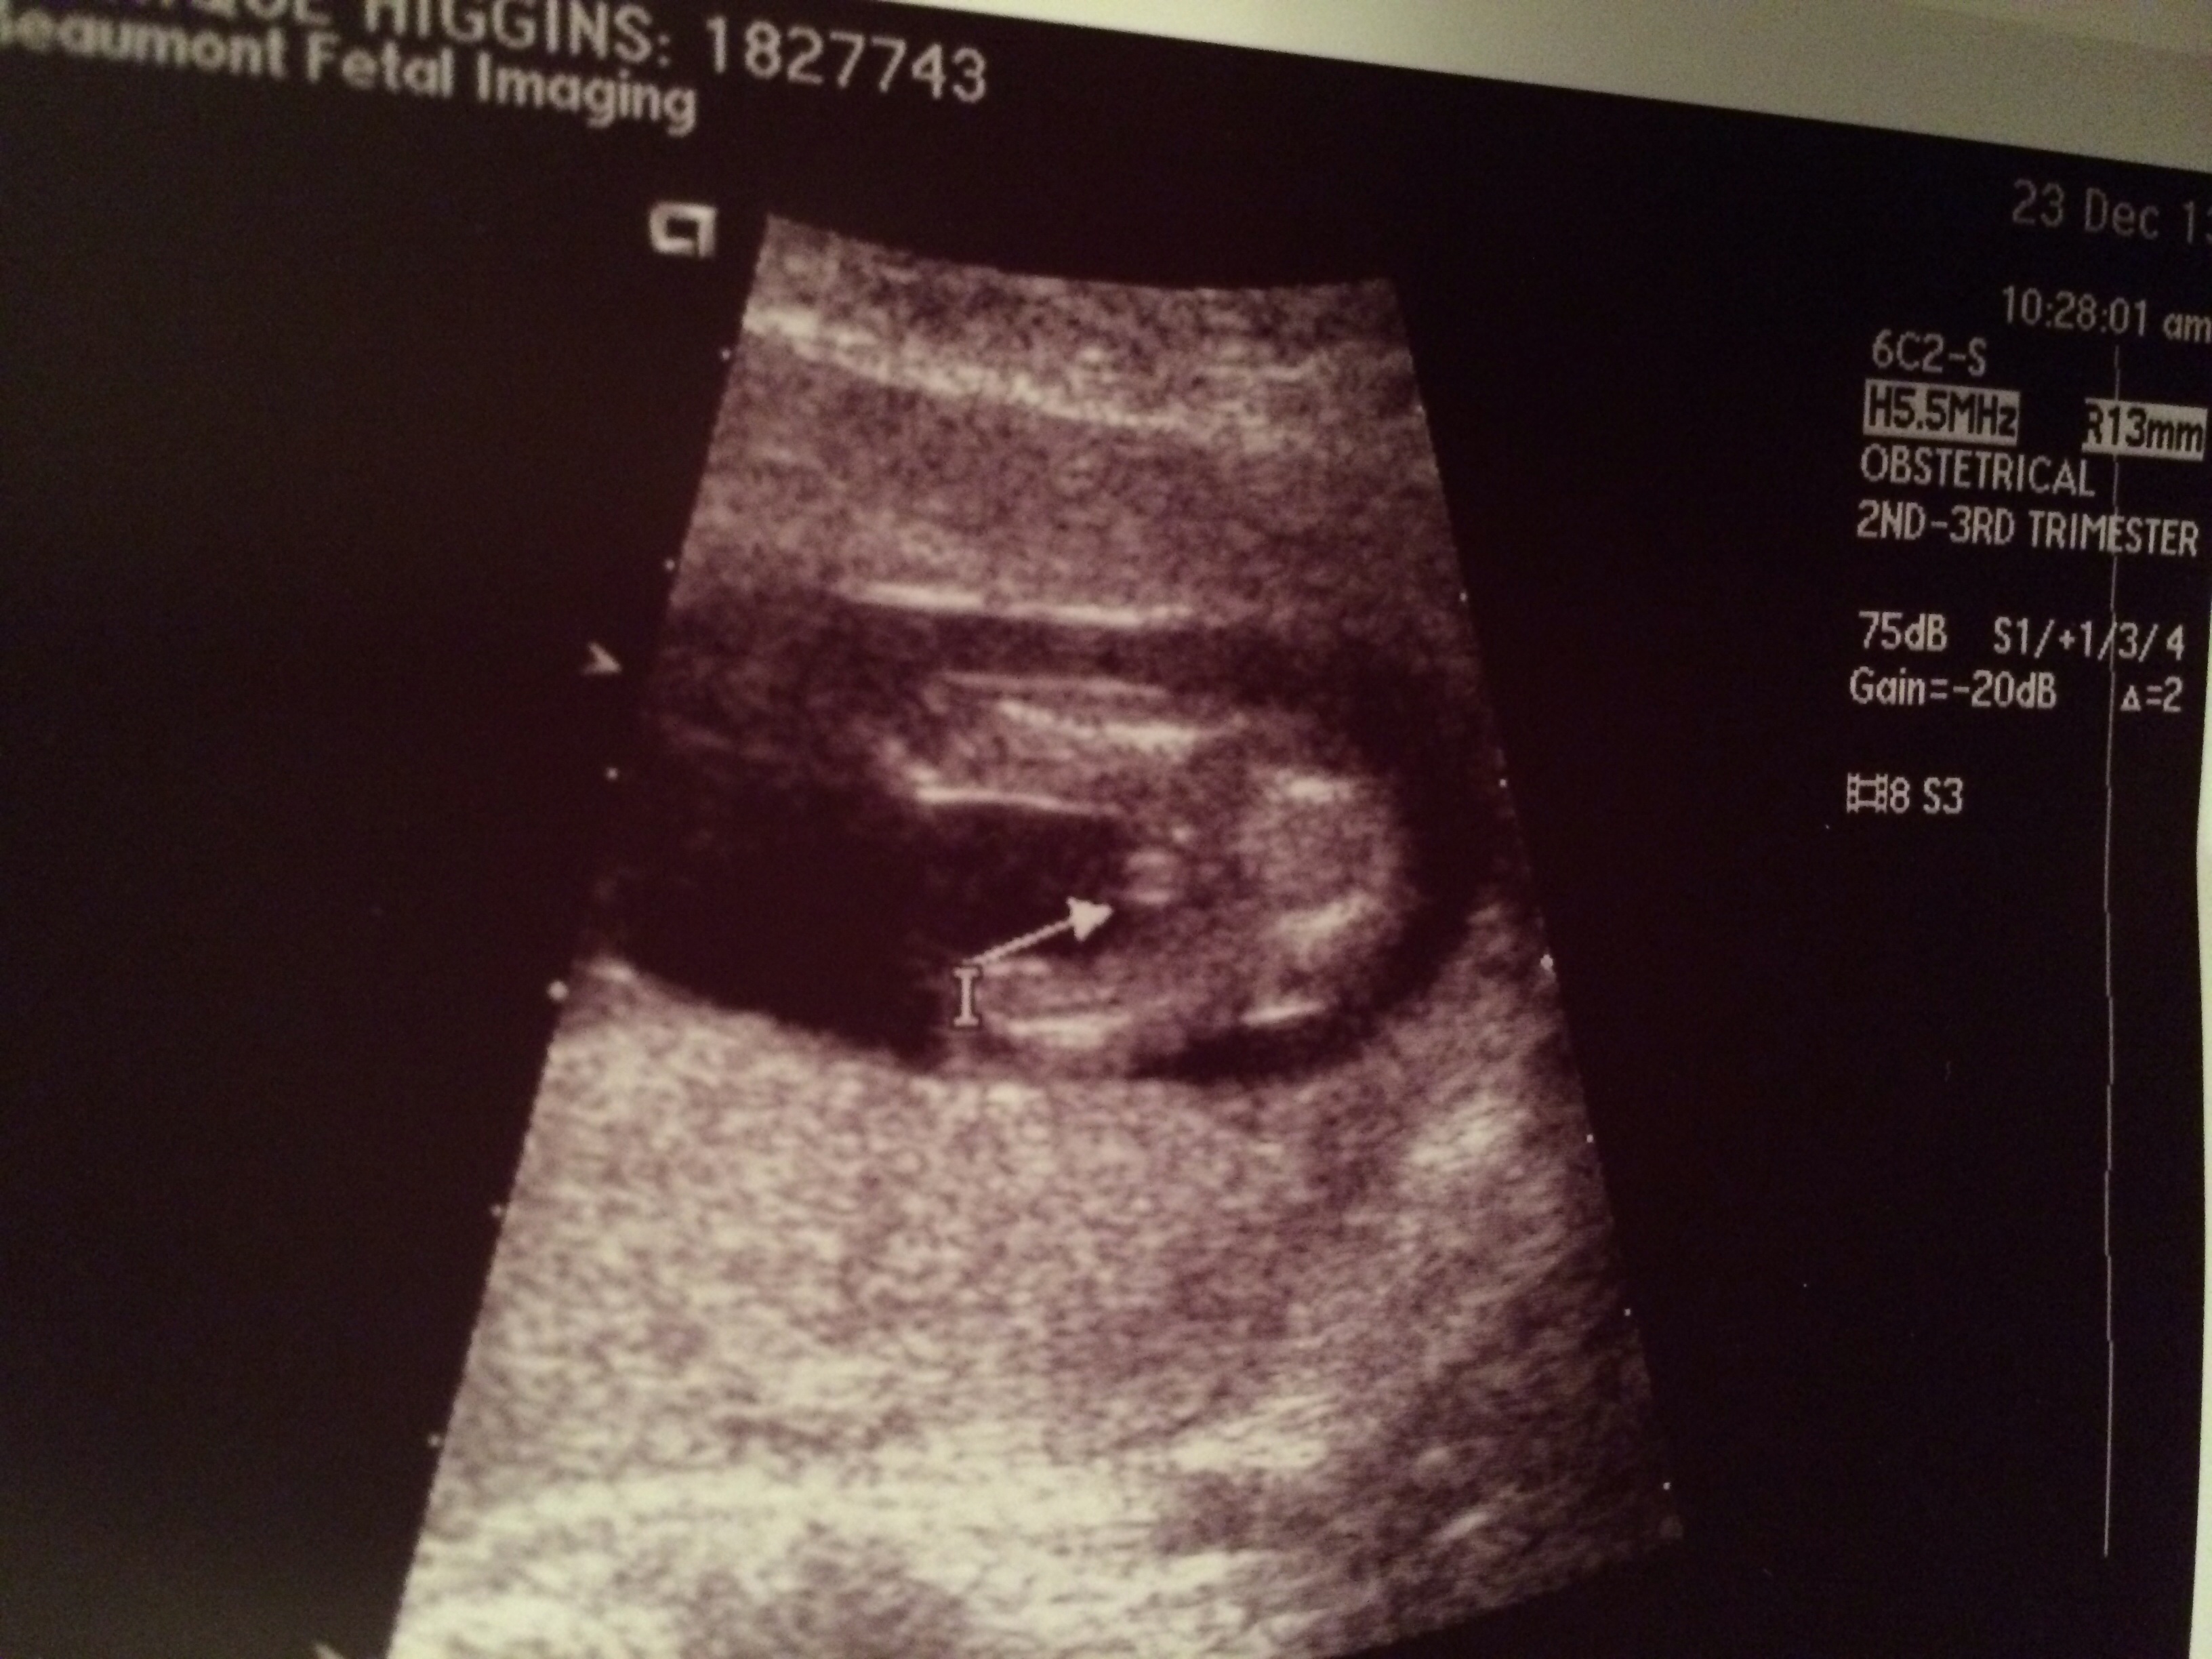

Ultrasound Today! Boy or Girl?

They said it's too early to tell... I'm 13w5d